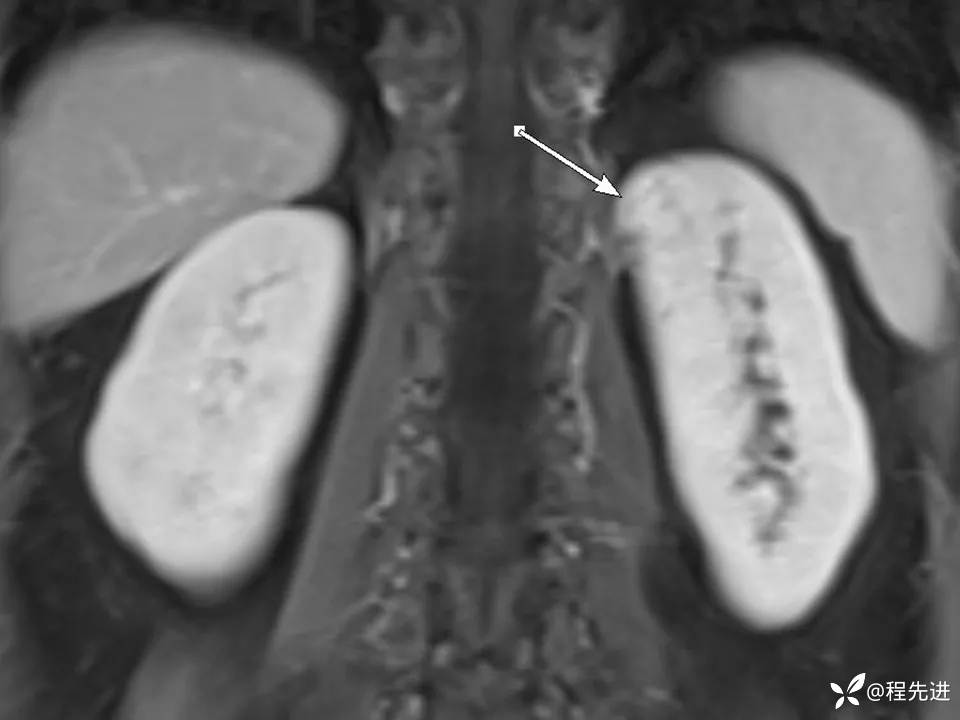

患者性别:女

患者年龄:67岁

简要病史:体检发现左肾占位,无临床症状,实验室检查无殊。

CT、MRI平扫+增强: